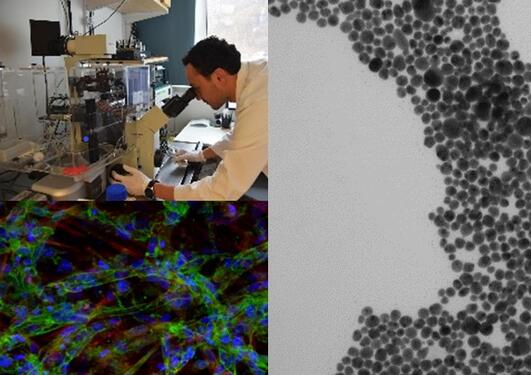

The laboratory-based testing methods include chemical analysis, physico-chemical characterization, biomechanical characterization and simulation, radiostereometric analysis, cell culture studies as well as analyses of retrieved materials and tissue, which establish the link to clinical research and registry studies.